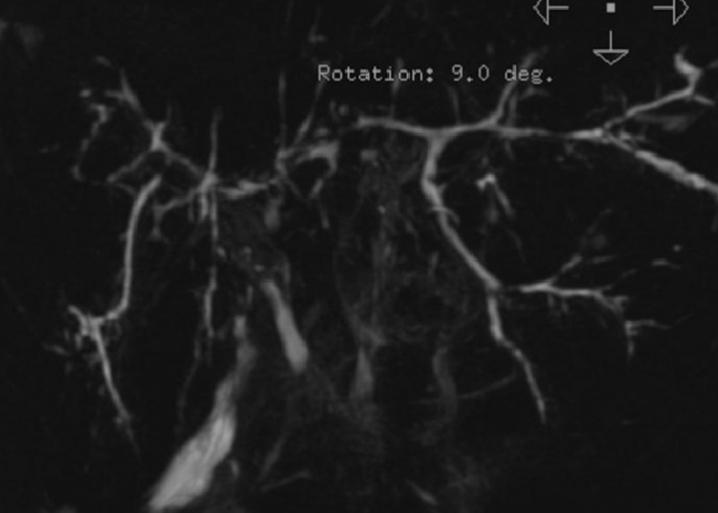

Cholangio Irm

Publié par : Kamal nadifi

Cholangiocarcinome du cholédoque détecter sur un cholangio-IRM.

Publié par : Kamal nadifi